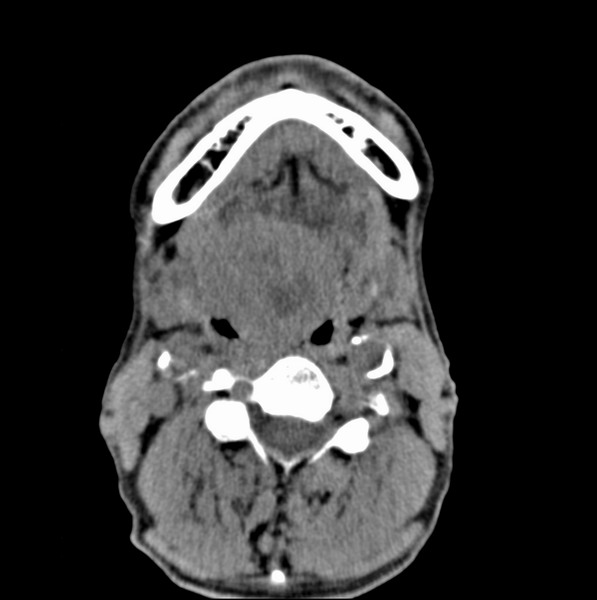

标题: CT19620:舌根肿物

男、60、舌根肿物。

舌跟软组织肿块,较大有坏死,钙化。结合年龄一般是恶性肿瘤。

直接取活检啊,舌头上的问题也做ct,mr还有点作用

舌根部较大软组织肿块,其内见坏死低密度区及钙化影;考虑舌根癌可能。

舌根癌可能性大。